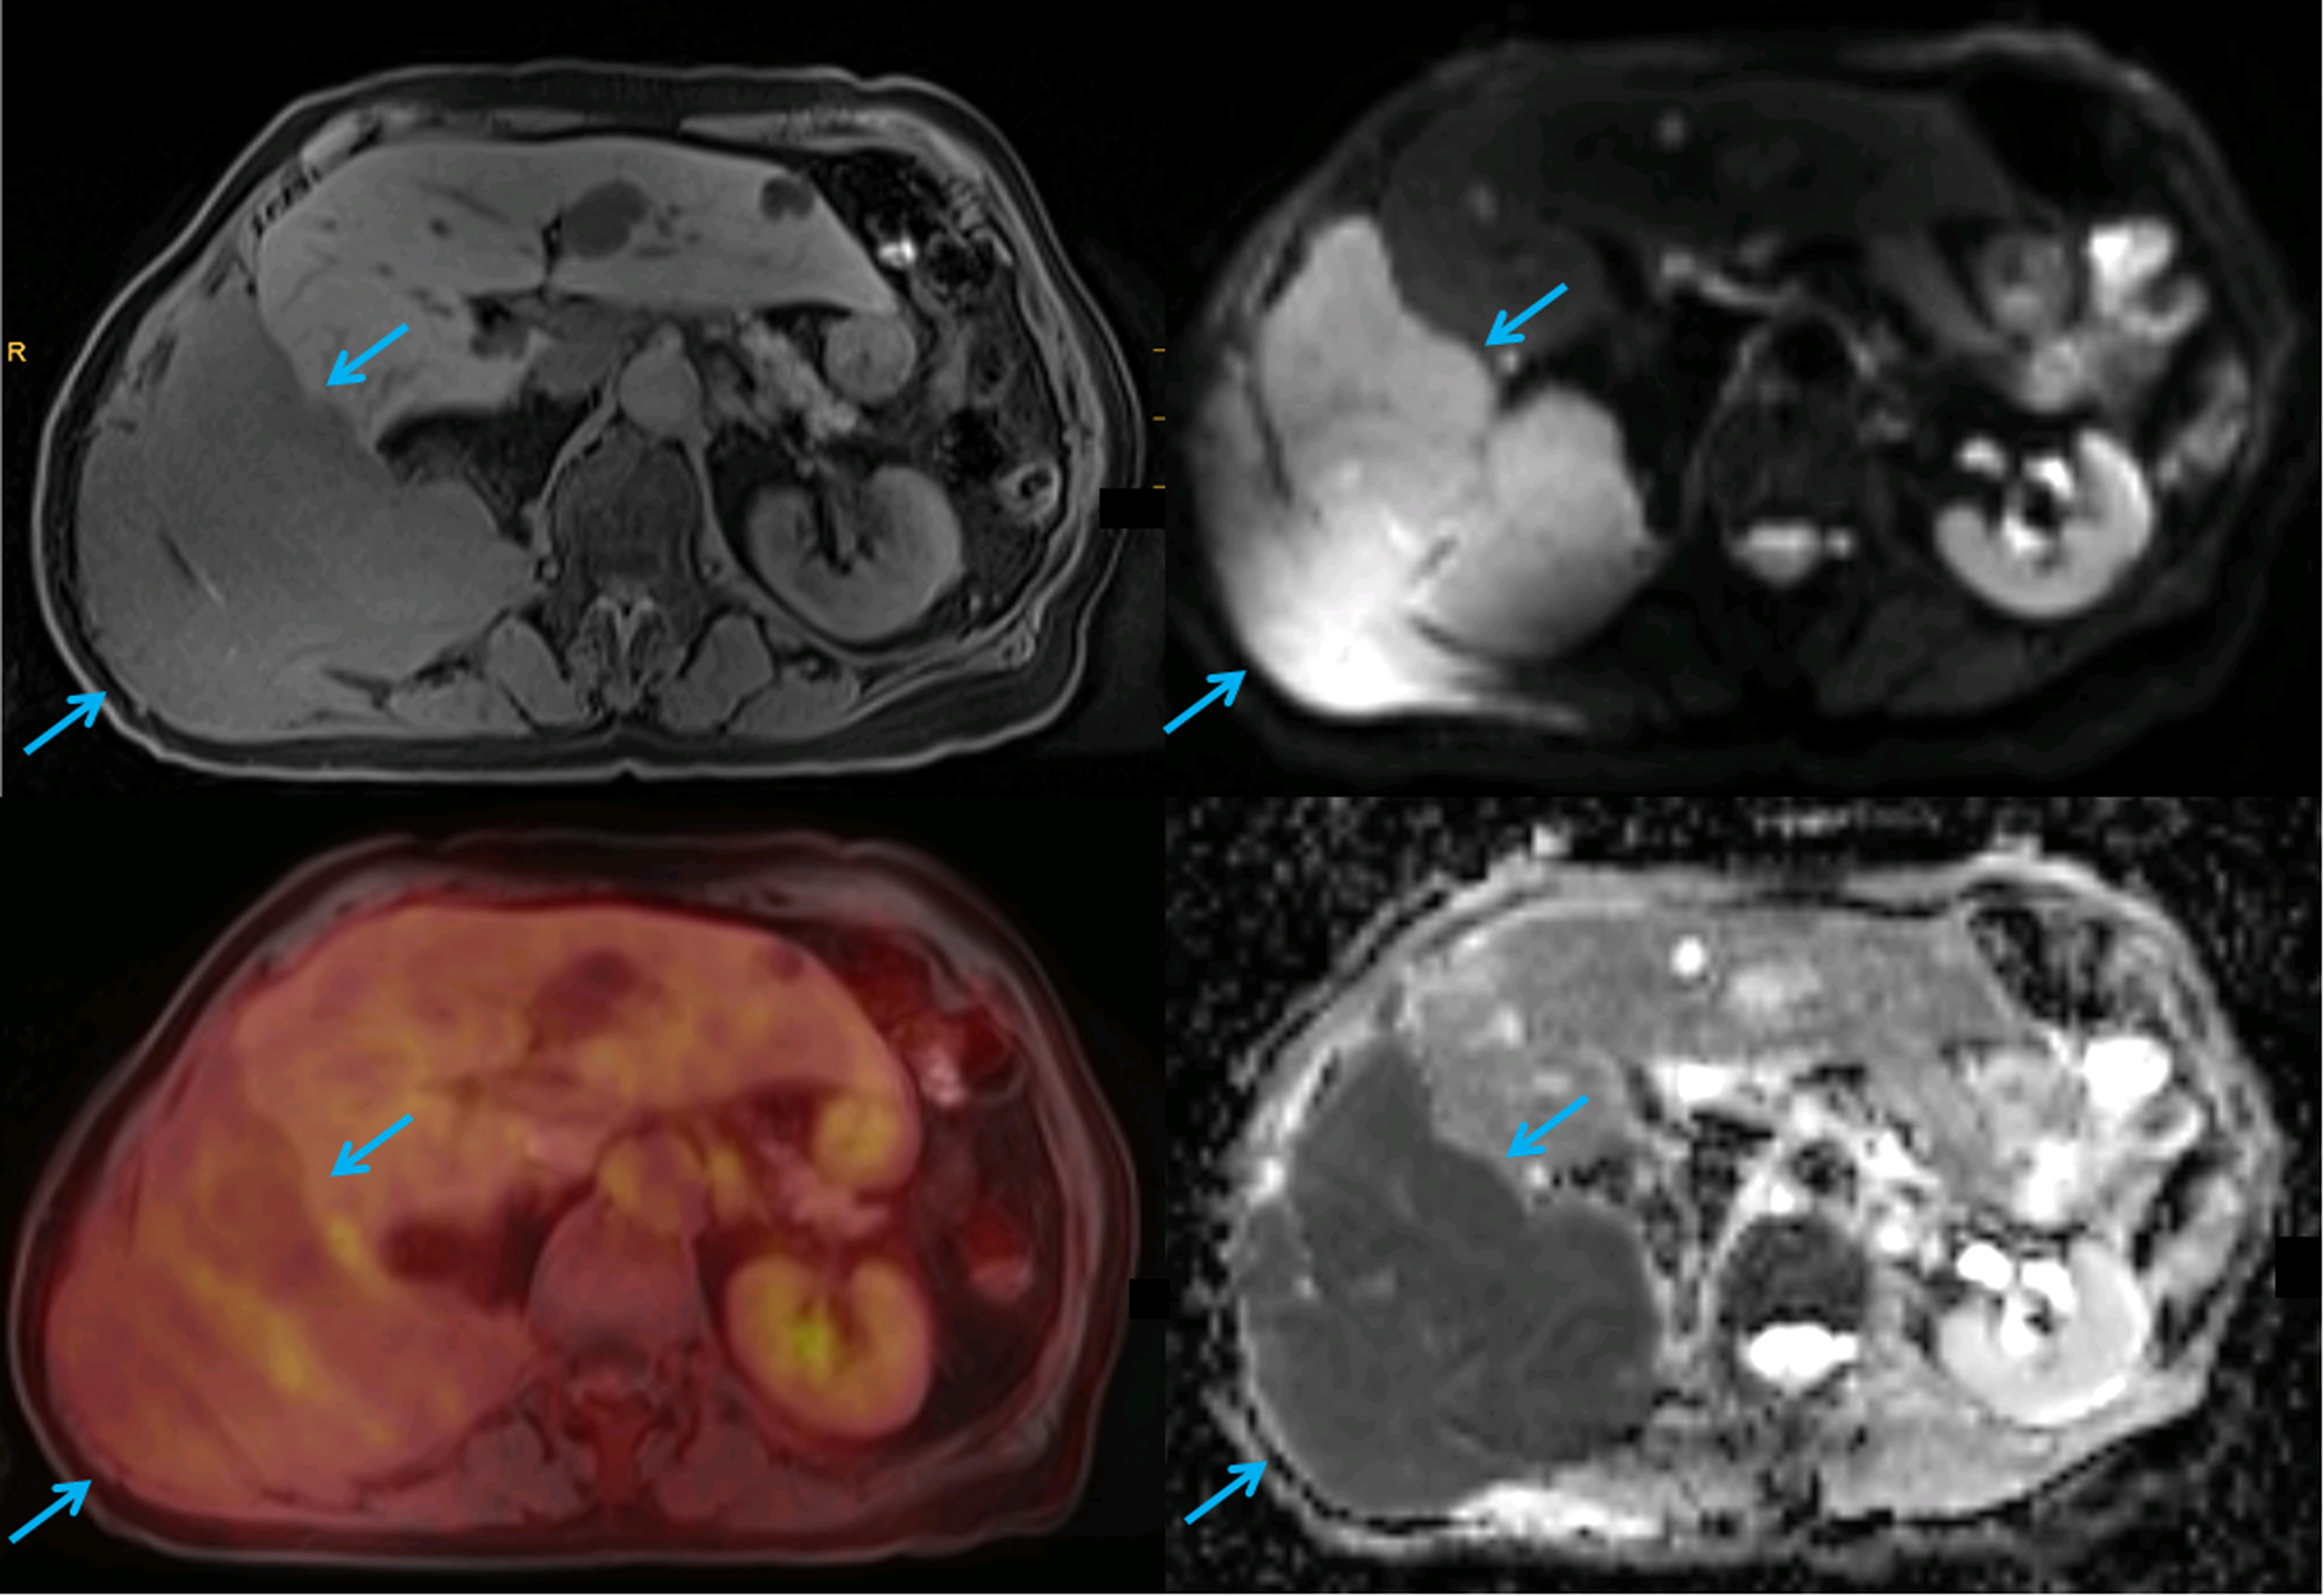

According to the current Lugano classification of the International Conference on Malignant Lymphomas (ICML), the two preferred imaging techniques for assessment of disease extent, disease staging and treatment response assessments are FDG-PET/CT and contrast-enhanced CT (CE-CT) ( ; ). Since the vast majority of lymphoma subtypes show an elevated glucose metabolism, FDG-PET/CT is generally the preferred test in lymphomas ( ; ). FDG uptake is considerably higher in aggressive NHL as well as Hodgkin lymphoma, with typical maximum standardized uptake values (SUV max ) between 10 and 30. Other, more indolent subtypes, including follicular lymphoma, show moderate, but still elevated FDG uptake relative to the background. However, some very slowly growing lymphomas such as the MZL group (which consists of nodular, splenic, and MALT variants), CLL/SLL, lymphoplasmacytic lymphoma (macroglobulinemia of Waldenström), and also cutaneous T cell lymphomas show a variable, frequently very low FDG uptake ( Fig. 9.1 ) ( ; ). It is for the latter group that PET/CT is not recommended by the ICML, and thus, CT remains the standard test.

Figure 9.1, A 65-year-old patient with macroglobulinemia Waldenström. A large soft-tissue mass infiltrating through the right posterior abdominal wall (blue arrows) is well visible on the T1-weighted fat-saturated MR image (top left) and shows high signal on DWI (top right) and low signal on the ADC map (bottom right), consistent with diffusion restriction and high cell density. However, due to the slow growth, the lesion shows low FDG uptake on the fused color-coded PET/MRI image (bottom left), similar to physiological liver uptake.